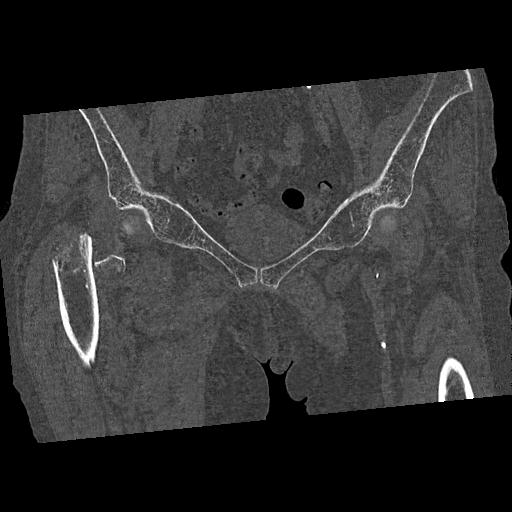

100703 1/27 両股正面+軸 1/29 両股正面+軸 94歳女性 パンソンロン

46666 1/28 両股正面+軸と 1/26 右手関節 2R 76歳女性 右転子部骨折

37 1/18 両股正面+軸 1/22 2R 86歳女性 右転子下

82084 1/14 1/20 股関節 2R 78歳男性 右人工骨頭

91569 3/25 両股正面とラウエン 70歳女性 人工骨頭+バンクーバー